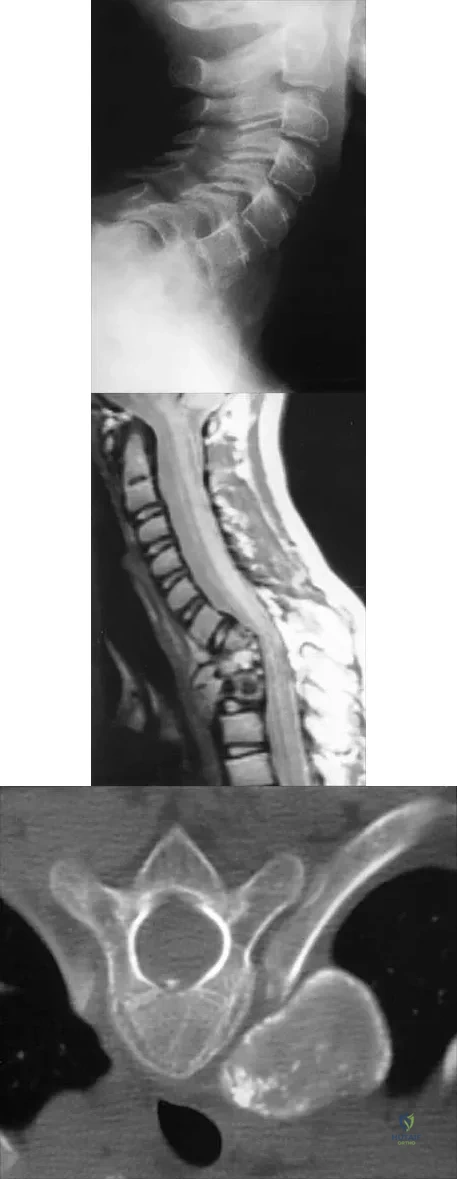

A 10-year-old girl has been referred for evaluation of a prominence at the lower cervical spine. The patient is asymptomatic, and the examination reveals no evidence of neurologic abnormality. A radiograph and CT scans are shown in Figures 12a through 12c. What is the most likely diagnosis?

Explanation

Tuberculosis is uncommon in the cervical spine but has a relatively greater incidence in young children. In a review of 40 patients with lower cervical spine involvement (C2 to C7), 24 were younger than age 10 years at presentation. In children, the disease is characterized by more extensive involvement with the formation of large abscesses. In older patients with lower cervical tuberculosis, the disease is more localized but is more likely to cause paraplegia. Four-drug antituberculosis therapy should be used. For patients with pain or neurologic dysfunction, anterior excision of diseased bone and grafting are indicated. Whether vertebral body excision and grafting should be done in an asymptomatic 10-year-old child is debatable. The CT scan shows a large "cold" abscess that is partially calcified. Hsu LC, Leong JC: Tuberculosis of the lower cervical spine (C2 to C7): A report on 40 cases. J Bone Joint Surg Br 1984;66:1-5.

- Loder RT: The cervical spine, in Morrissy RT, Weinstein SL (eds): Lovell & Winter's Pediatric Orthopaedics, ed 4. Philadelphia, Pa, Lippincott-Raven, 1996, pp 739-789.